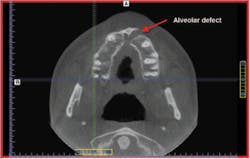

A patient with a previously grafted alveolar cleft was recently referred to our clinic by another surgical practitioner for implant placement. While the referring practitioner indicated that the grafted area was an acceptable recipient site based on available 2–D imaging, the cone beam scan showed grossly insufficient bone into which to place the implant. This is clearly evident on the images (Fig. 1, 2). If implant surgery had been instituted based on the information provided by the 2–D images, without this additional and vital information, the patient's confidence could have been lost, as well as potential referrals to his friends and family, possibly causing a negative impact to ROI. In this case, however, a 3–D computer model clearly pointed out the bony deficiency prior to surgery.